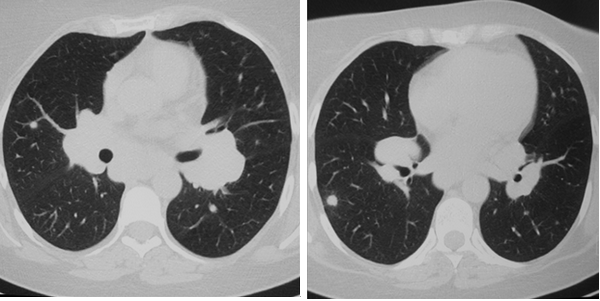

Симптом «матового стекла» (36%) визуализировался в виде небольших, ограниченных участков снижения прозрачности лёгочной ткани (рис. 2).

Рис. 2. РК-томограммы (режим лёгочного окна) пациента Г., 28 лет, с саркоидозом легких и ВГЛУ. Стрелкой указаны участки «матового стекла»

На ранних стадиях заболевания симптом «матового стекла» мог быть единственным, либо сочетаться с увеличением ВГЛУ.

Одним из наиболее часто наблюдаемых нами при КТ признаков саркоидоза являлся симптом диссеминации (70-80% случаев). При этом превалировала картина интерстициальных изменений с ретикуло-нодулярными фокусами размерами около 1-2 мм. Распределение теней было, главным образом, перилимфатическим с локализацией в средних и верхних легочных зонах (рис. 3). Реже визуализировались гроздевидные очаги округлой или неправильной формы до 6 мм в диаметре, с преимущественно субплевральной локализацией.

Рис. 3. На РК-томограммах больной Ж., 49 лет, определяется двухсторонняя диссеминация с преимущественной локализацией в среднем легочном поясе